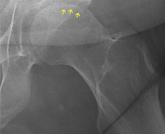

ArticleOsteonecrosis of the femoral head with subchondral collapseAuthor:Hiba K. Anis, MDPublish date: August 1, 2019A 45-year-old woman had been taking corticosteroids long-term after organ transplant.Read More